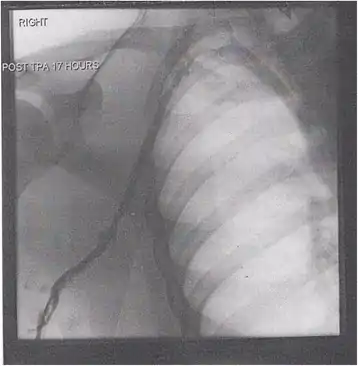

Thrombolysis is the injection of an enzyme into the veins to dissolve blood clots, and while this treatment has been proven effective against the life-threatening emergency clots of stroke and heart attacks, randomized controlled trials[139][140][141] have not established a net benefit in those with acute proximal DVT.[5][142] Drawbacks of catheter-directed thrombolysis (the preferred method of administering the clot-busting enzyme[5]) include a risk of bleeding, complexity,[lower-alpha 12] and the cost of the procedure.[125] Although, while anticoagulation is the preferred treatment for DVT,[125] thrombolysis is a treatment option for those with the severe DVT form of phlegmasia cerula dorens (bottom left image) and in some younger patients with DVT affecting the iliac and common femoral veins.[12] Of note, a variety of contraindications to thrombolysis exist.[125] In 2020, NICE kept their 2012 recommendations that catheter-directed thrombolysis should be considered in those with iliofemoral DVT who have "symptoms lasting less than 14 days, good functional status, a life expectancy of 1 year or more, and a low risk of bleeding."[138]